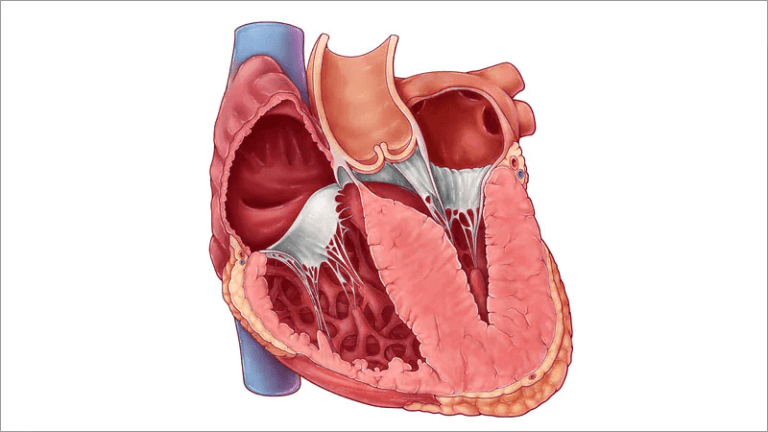

O que é a Miocardiopatia Hipertrófica? A Miocardiopatia Hipertrófica (MCH) é uma doença primária do músculo cardíaco, caracterizada por hipertrofia (aumento da espessura) do ventrículo

Estenose Aórtica: Valvas Cardíacas e as portas dentro do seu do Coração Imagine o seu coração como uma casa com quatro cômodos, cada um com